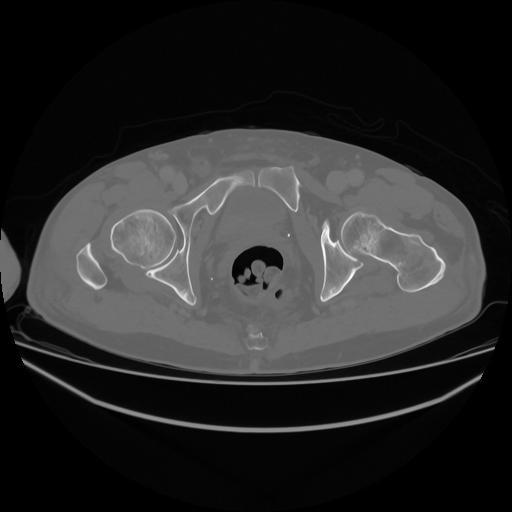

5 CUERPO,CE,Vol,1.0,CUERPO,,